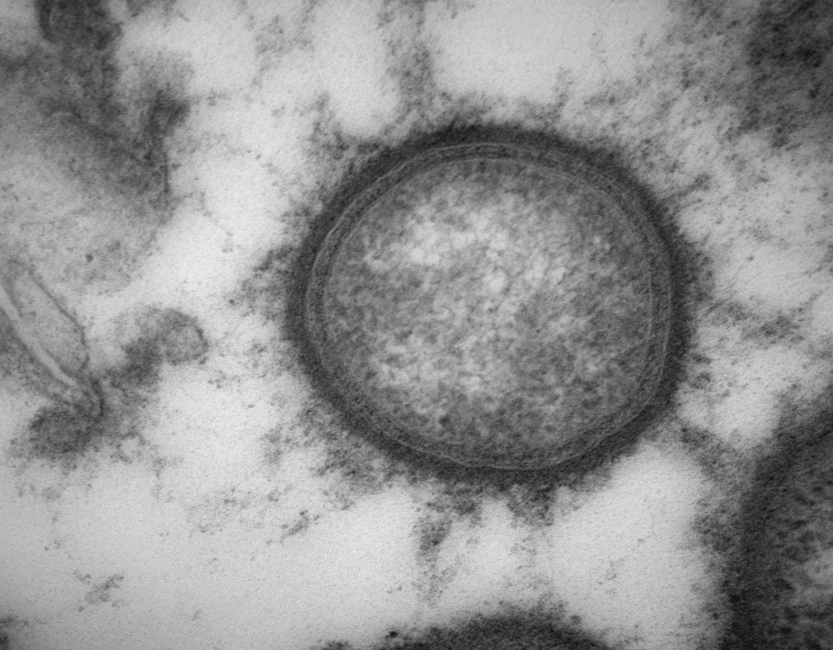

The paper, published in the Journal of Oral Microbiology, demonstrates that P. gingivalis uses sphingolipids – unique membrane lipids that play a multifaceted role in its survival and stress responses – to evade neutrophils, which represent the body’s initial inflammatory response to bacterial attacks.

“Previous studies showed that sphingolipid-carrying outer membrane vesicles (OMVs) released by P. gingivalis can limit the inflammatory response of macrophages, and now we have shown for the first time that the response by neutrophils is also  limited when  sphingolipid-containing OMVs are produced,” said Prof. Alpdogan Kantarci, D.D.S., Ph.D., C.A.G.S, who led the study alongside ADA Forsyth Professor Mary Ellen Davey, Ph.D., and lead author Dr. Fatma Oner, D.D.S, Ph.D.

P. gingivalis‘ survival can send yet more harmful ripple effects throughout the body, with its OMVs acting as nano-sized “microbullets.” These bullets release from P. gingivalis membranes and disperse pathogenic effects into surrounding tissues and the vascular system, ultimately having far-reaching effects.